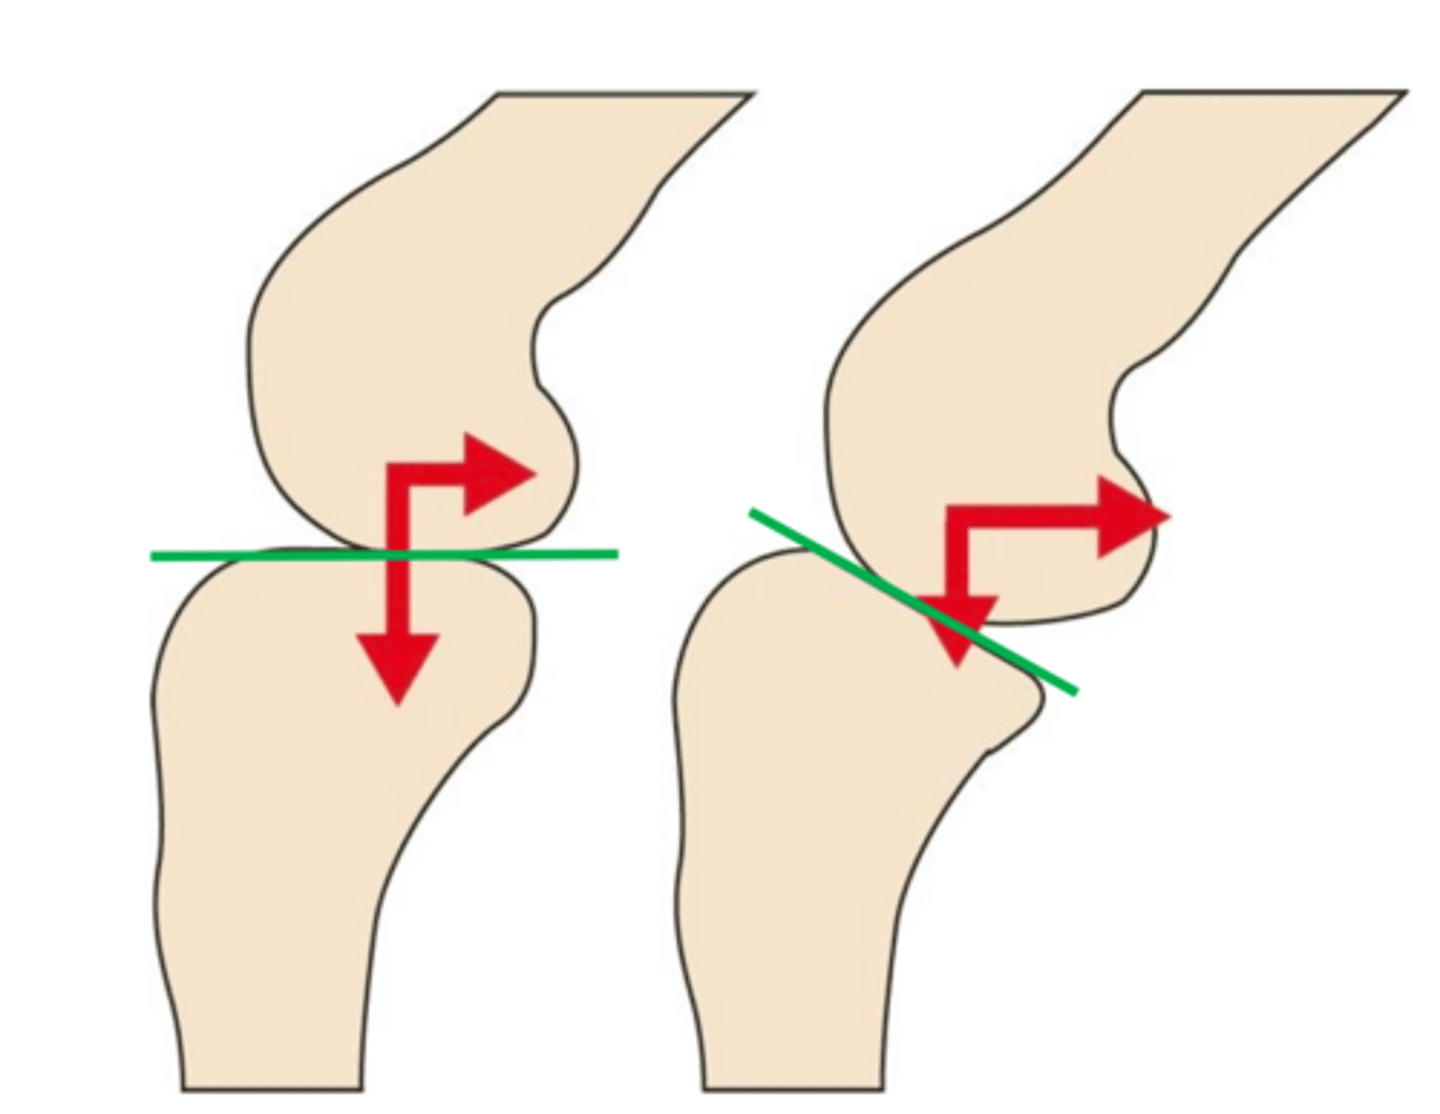

cranial tibial thrust force

when the slope of tibial plateau is NOT anatomically oriented perpendicular to patellar lig, it leads to ____

1. caudally directed slop of tibial plateau results in shear force

2. creates abnormal tibial translation in CCL deficient stifle

in terms of stifle mechanics when the tibia is loaded...

cranial tibial thrus/CTT

the shear component of compressive force is called ____ and is normally passively constrained by the CCL

slope of the tibial plateau

the CTT (cranial tibial thrust) is proportional to the ____